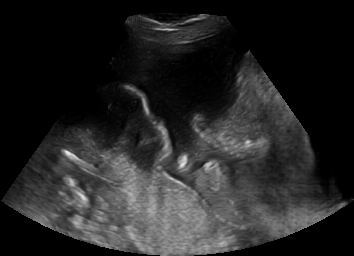

Real in-vivo images. 22 ultrasound sequences were collected using a GE Voluson E8 machine during standard fetal screening exams of 8 patients. Each sequence is several seconds long. We extracted all 4427 frames and resize them to , see Fig. 2 for some examples. The resulting image set was randomly split into training-validation-test sets by a 80-10-10% ratio.